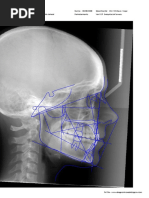

Análisis de Ricketts resumido

Unidad de Análisis: Radiografías Lateral de cráneo en las que se analizaron las medidas cefalométricas según Análisis

Cefalométrico Resumido de Ricketts.

Figura 1.

Comportamiento del Eje Facial del Análisis de Ricketts Resumido en pacientes atendidos de 18 años de edad en la

Especialidad de Ortodoncia UNFLEP- Estelí, de agosto 2021 – noviembre 2024.

En la Figura 1 se muestra el comportamiento del Eje Facial en los 24 individuos de estudio, según la norma del Análisis

de Ricketts Resumido, es de 90° ±3. Se observó que 7 individuos (29%) de la muestra total se encontraron en los

límites de la norma, sin embargo 11 individuos (46%) presentaron valores menores, que corresponden a ejes faciales

cerrados, común en patrones Clase II con tendencia a crecimientos vertical que coincide con los hallazgos encontrados

de (Mendez, 2009) y difiere con los datos reflejados en (Podadera Valdes, 2003). Los valores que se presentaron

mayores de la norma fueron seis individuos (25%) que correspondería a ejes faciales abiertos o patrones Clase III con

tendencia al crecimiento horizontal.